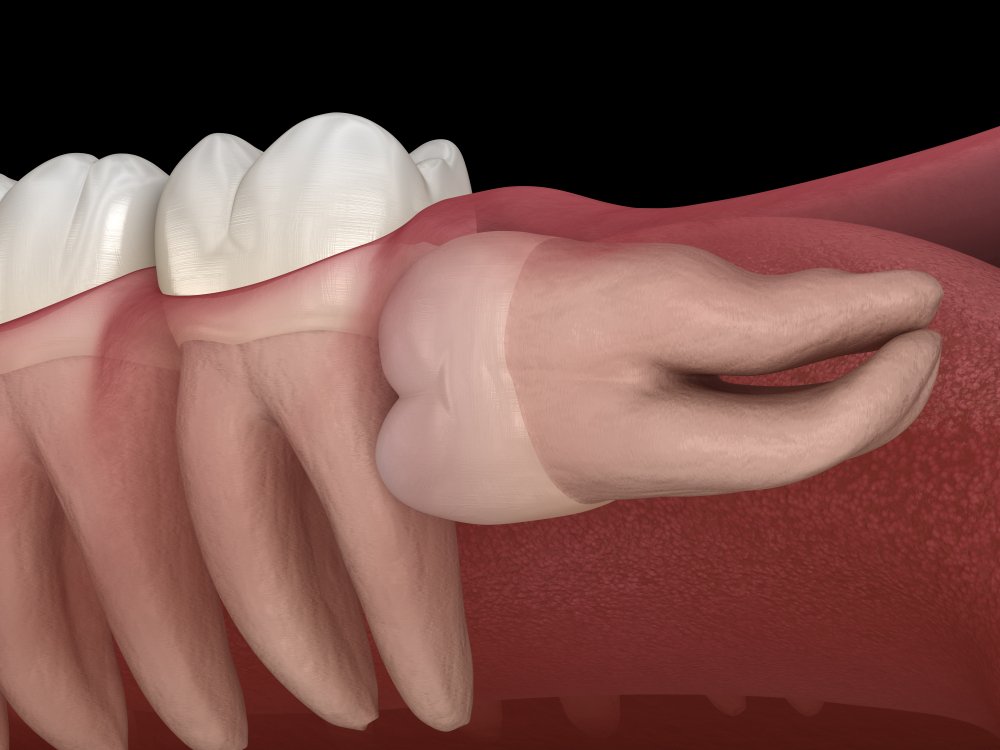

Problemele care pot să apară în cazul molarilor de minte se referă, în special, la poziția în care ei se dezvoltă și la modul în care erup. Din acest punct de vedere, următoarele situații sunt motive serioase pentru care extracția ar putea fi recomandată sau chiar obligatorie:

- Nu au suficient spațiu să se dezvolte. Atunci când măselele de minte nu au suficient spațiu să se dezvolte normal, pot să-și facă loc cu forța. Practic, se împing în molarii lângă care cresc. Astfel pot să apară așa-numiții dinți încălecați sau se poate ajunge chiar la deteriorarea molarilor din apropiere; pot să apară înghesuiri dentare un un efect de domino generalizat.